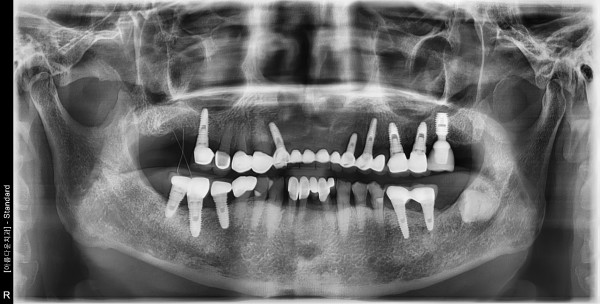

70대 남성 임플란트 식립

2d74e31fb819137f530da93a17333eb6_1759282